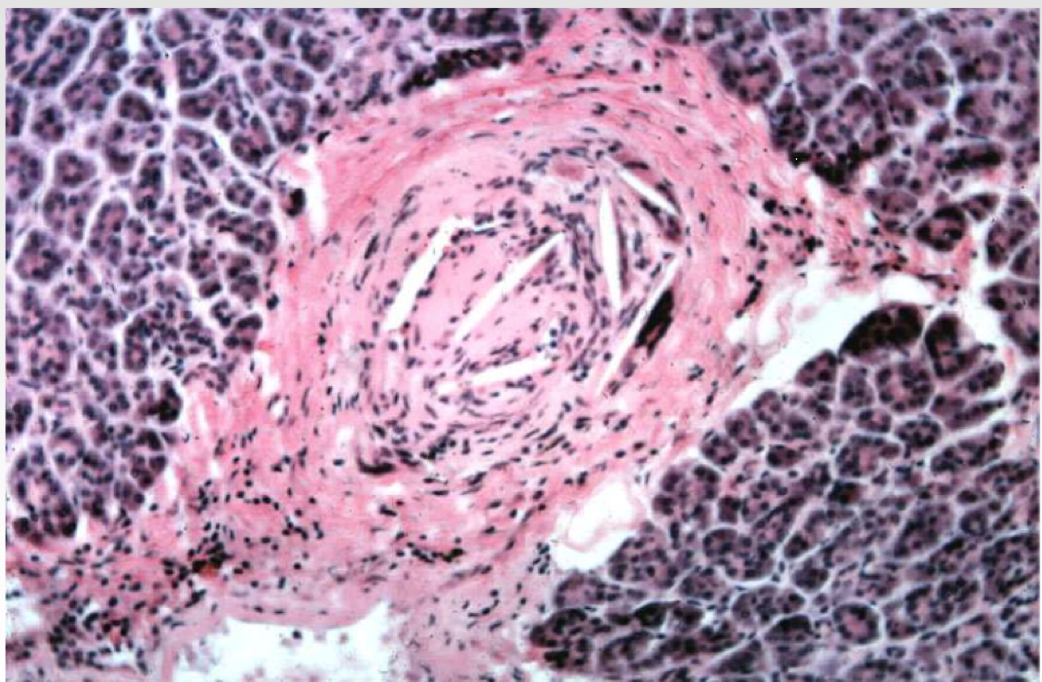

What is this?

Cholesterol emboli

When you see cholesterol clefts think about atherotic embolic dz

Aneurysm, aortic dissection

Cholesterol embolization due to aneurysm